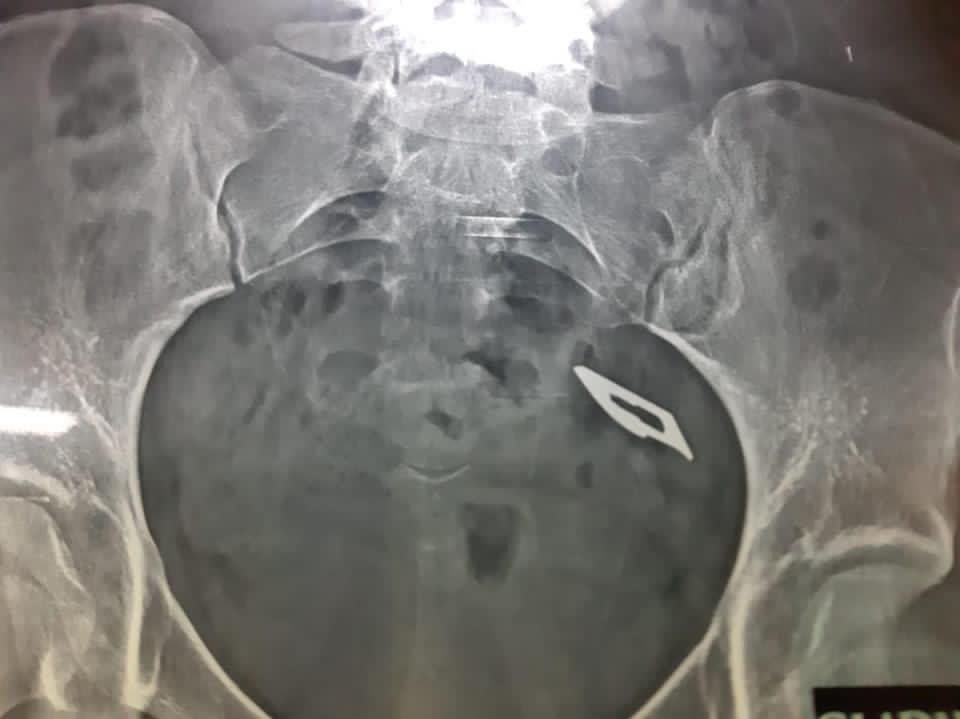

استخراج مشرط جراحي من داخل أمعاء فتاه بمستشفي المنصورة التخصصي

نجح فريق طبي بمستشفى المنصورة التخصصي التابعة لأمانة المراكز الطبية المتخصصة، من إجراء عملية نادرة بالمنظار الطبي لفتاة تعاني من اضطراب نفسي تبلغ من العمر 16 ابتلعت مشرط طبي، واستطاع فريق الجهاز الهضمي والمناظير بمستشفى المنصورة التخصصي، من استخراج المشرط الجراحي من داخل أمعائها باستخدام المنظار، ودون الحاجة إلى تدخل جراحي، والحالة بصحة جيدة وتم خروجها من المستشفى.